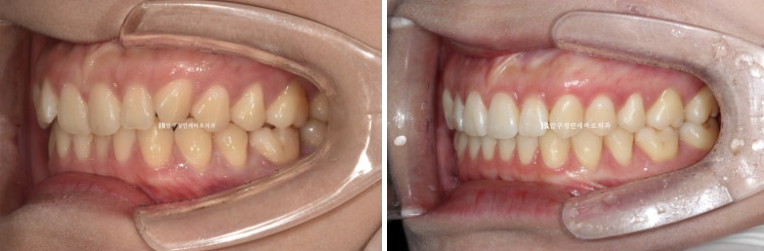

전 후 보겠습니다.

24.02~24.11

문제의 우측 II급 교합관계가 거의 I급으로 좋아졌습니다.

고무줄을 열심히 껴준 덕입니다.

좌측교합은 원래 I급이고 위아래 어금니 교합이 좀 더 긴밀해졌습니다.